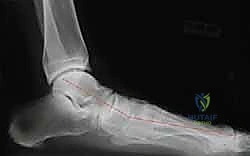

* الأشعة السينية (X-rays) أثناء الوقوف: صور بالأشعة السينية للقدم والكاحل أثناء تحمل الوزن (الوقوف). يتم قياس زوايا محددة (مثل زاوية ميري Meary's angle، وزاوية التغطية الزورقية الكاحلية Talonavicular coverage angle) لتقييم درجة الانهيار العظمي بدقة هندسية.